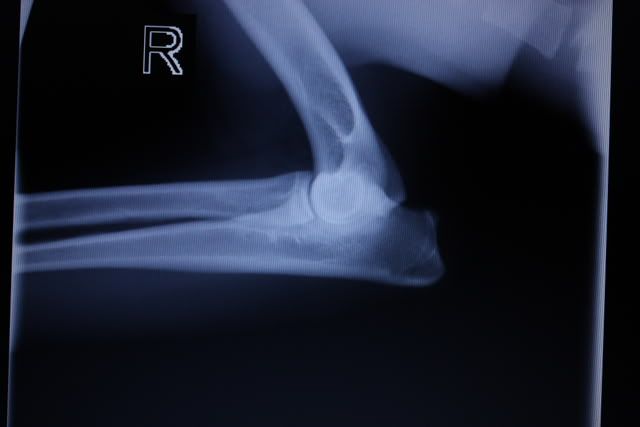

Er werden rontgenfoto's gemaakt van de heupen en de ellebogen.

Gelukkig is er een goede uitslag, zowel de heupen als de ellebogen zien er uitstekend uit.

Ik heb de foto's meegekregen met een mooi programma waarin ik ze kan open en inzoomen enzo.

Daarom heb ik maar een foto ervan gemaakt terwijl ik ze op de computer heb.

Het is dus niet echt heel duidelijk, maar geeft in ieder geval een idee.